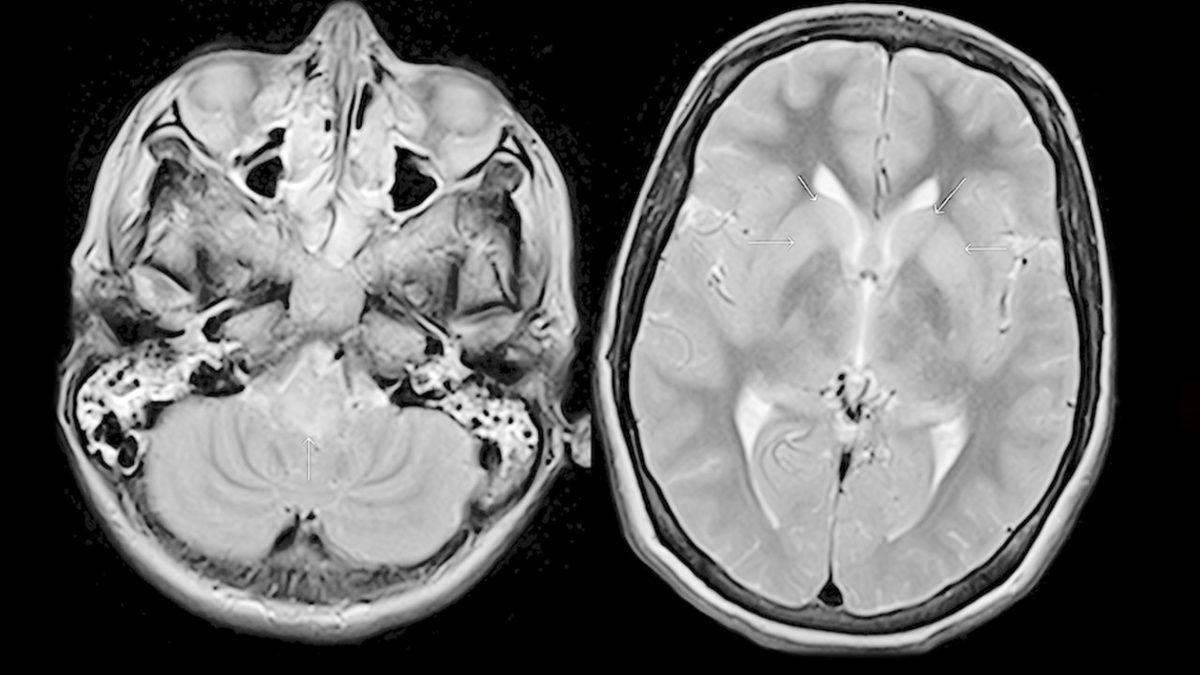

- Kuduz hastası bir kişinin hastaneye yatışının 16. gününde çekilmiş MR görüntüsü. (Ölümünden 4 gün önce)

Kuduz bir köpeğin ayak parmağınızdan ısırdığını varsayalım. Bu dakikadan sonra virüs, vücudunuzda ilerlemek için çalışmalara hemen başlayacaktır. Bunu yaparken de önüne çıkan tüm hücreleri enfekte eder ve ardından parçalar. Beynimize ulaşıp kuluçka süresi bitene kadar ise pek fazla belirti göremeyiz. Kuluçka süresi ise kuduz virüsünün türüne ve ısırıldığınız bölgenin beyne uzaklığına göre değişiklik gösterebilir. Genelde bu süre 2-3 ay olsa da 1 yıla kadar çıkabilir veya 1 hafta sürebilir.